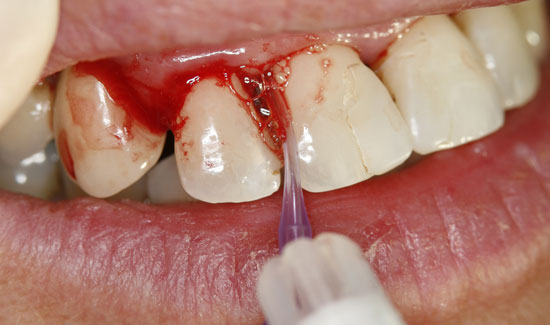

Die Patientin stellte sich in unserer Praxis vor mit der Frage der konservativen Erhaltbarkeit der Oberkieferfrontzähne bei chronischer Parodontitis. Wir fanden generalisierte Taschenbildungen (> 10 mm), Spontanblutungen und einen Lockerungsgrad 2/3, d.h. extraktionswürdige Zähne. Als Überbrückungsmaßnahme (Feiertagssituation) bis zu Sanierungsmaßnahmen boten wir ihr lokale Ozongasbehandlungen an.

Als Ozongasspender verwendeten wir Prozone, das mit Hilfe von Kunststoffansätzen Ozongas schmerzarm in die Taschen einzuleiten erlaubt. Die lokale Ozongas-applikation wurde dreimal im Wochenabstand wiederholt. Außerdem wurde die Patientin auf notwendige persönliche Hygienemaßnahmen aufmerksam gemacht. Wir konnten nicht nur die Blutungen stoppen, sondern den Lockerungs-grad der Zähne in einem stabilen Zustand (2) halten und die messbare Taschentiefe verringern.

Abb. 2: Klinischer Aspekt der Regio 12, Entstehung von Gasblasen am entzündeten Gewebe. Fortlaufende Absaugung in der Nähe des Einsatzgebietes